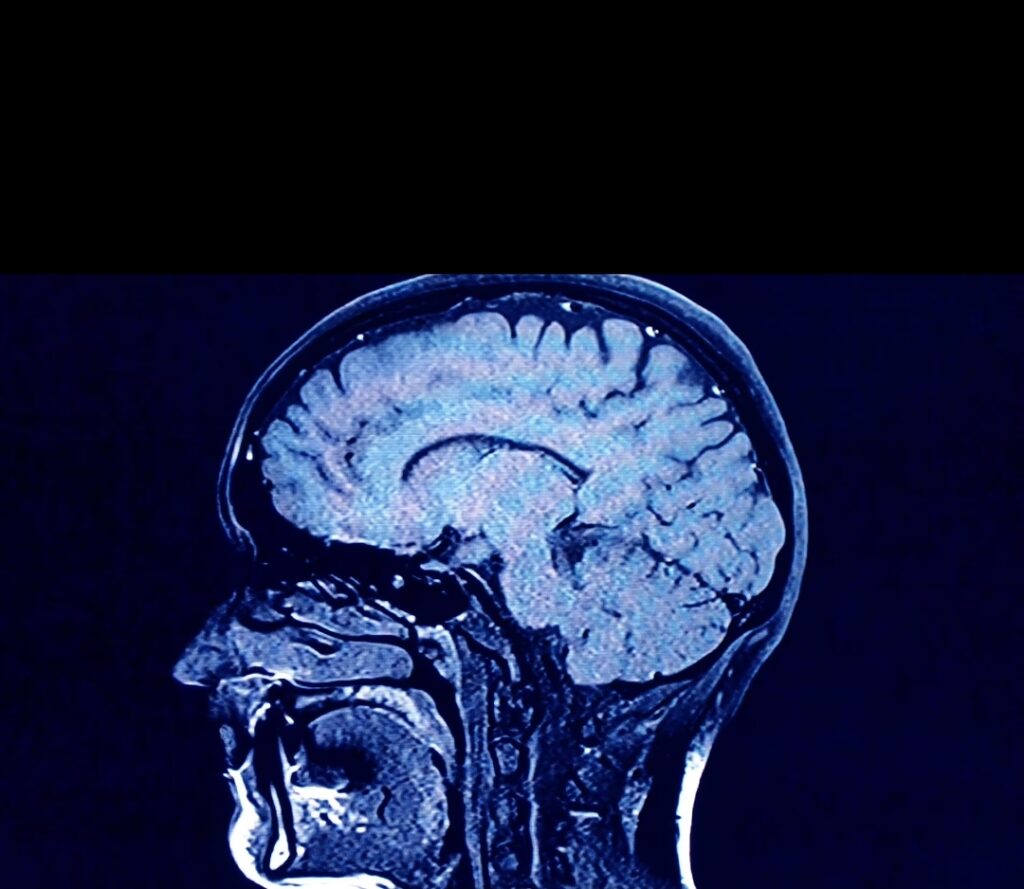

‘Beyin atıklarımız’ nereye gidiyor? Atıklar, hangi hastalıklar ve nasıl bir uyku düzeniyle ilişkili?

Bilim insanları beynin sağlıklı kalmak ve nörolojik hastalıklarla mücadele etmek için atık ürünleri nasıl dışarı attığını anlamaya başlıyor.

Beyin bu sistemin bir parçası değildir ve onun atık imha yolu, glimfatik sistem olarak bilinir. Karbon dioksit, hasarlı proteinler ve ölü hücreler gibi, enerji tüketen metabolik süreçlerin (vücudun düzgün çalışmasını sağlamak için vücutta sürekli çalışan tüm kimyasal süreçlerin) ürettiği atıkları temizler.